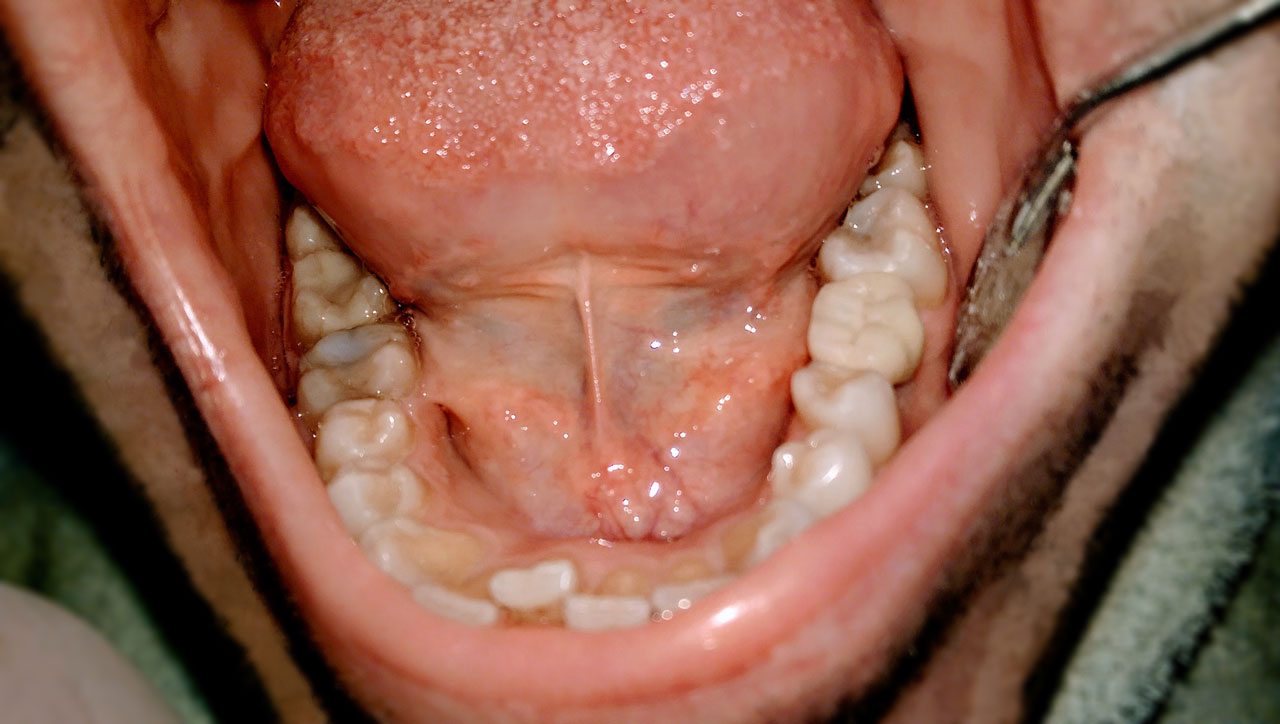

Rendelőnkben már több mint tíz éve végzünk sikeresen fogbeültetéseket. Az implantátumok alkalmazása a fogászatban ma már szinte minden foghiány pótlása esetén szóba jöhet, a teljes foghiánytól, illetve a sorvégi hiányoktól kezdve, a csak a hiányzó fogat pótló megoldásokig. Implantált betegeink között volt 20 és 80 éves is, és mindenkinek sikerült kortól függetlenül a legjobb fogpótlást készíteni. Célunk az, hogy a már kialakult foghiányt úgy pótoljuk, hogy ne csak a rágóképességet állítsuk helyre, hanem az arc harmóniáját is, hiszen a szép mosoly növeli önbizalmunkat és komfortérzetünket.